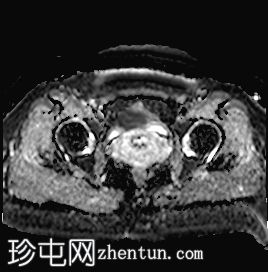

轴位

STIR序列

可见子宫外腹腔内妊娠囊,内含胎儿组织。

该妊娠囊向后推移子宫,并与剖宫产瘢痕凹陷处紧密相连。

该妊娠囊与相关肠袢无法分离。可见其与性腺血管密不可分,且性腺血管明显突出。

胎盘位于妊娠囊后方,紧贴子宫前壁。

沿妊娠囊下缘可见一处异质性局灶性积液,最大轴向尺寸约为 8.4 × 5.5 cm,T1 加权像呈异质性高信号,T2 加权像呈异质性中等信号,T1 脂肪抑制序列未见信号下降,提示为血液成分。该积液压迫膀胱。

可见周围脂肪间隙呈条索状改变。

左侧卵巢无法辨认。

右侧卵巢未见实性或囊性肿块。

子宫体积增大,后倾,子宫内膜厚度约 1 cm,子宫下段前壁可见局灶性变薄(既往子宫瘢痕)。子宫连接区完整,未见肌层肿块。可见子宫内膜腔边缘有血性分泌物。